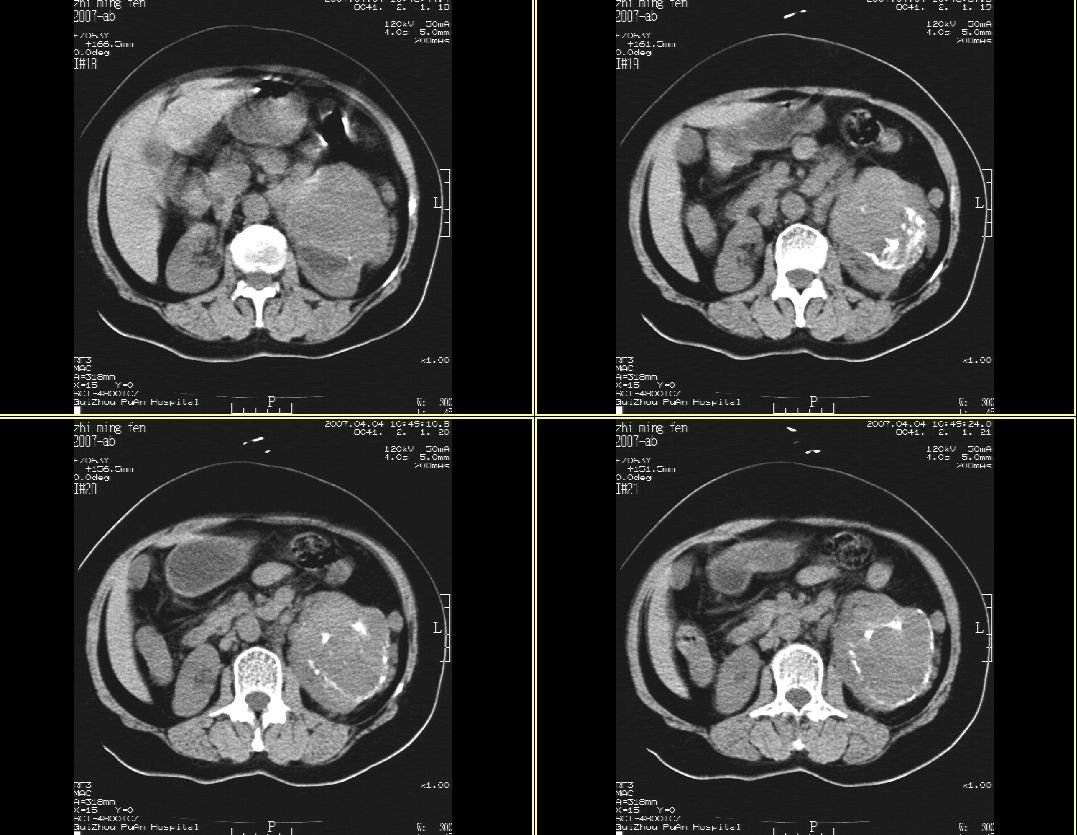

以下是引用hhcckk在2007-4-9 9:18:00的发言:[br]我认为就是一个病灶,病灶上端密度较均匀,下方有明显的钙化,部分呈不完全的环状,考虑肾癌[br]1、肾癌的特征性ct表现为肾实质的占位,局部隆起外突[br]2、肿瘤内的钙化常见,多发生在肿瘤内部,也可以在肿瘤周边呈弧型或不完全的环行钙化[br]3、最常见的三大症状,血尿,腰痛,包块此病人也较符合,增强吧

以下是引用swyyy2007在2007-4-9 18:42:00的发言:[br]支持左肾癌累及肾窦肾盂,左肾积水 [br] [br]